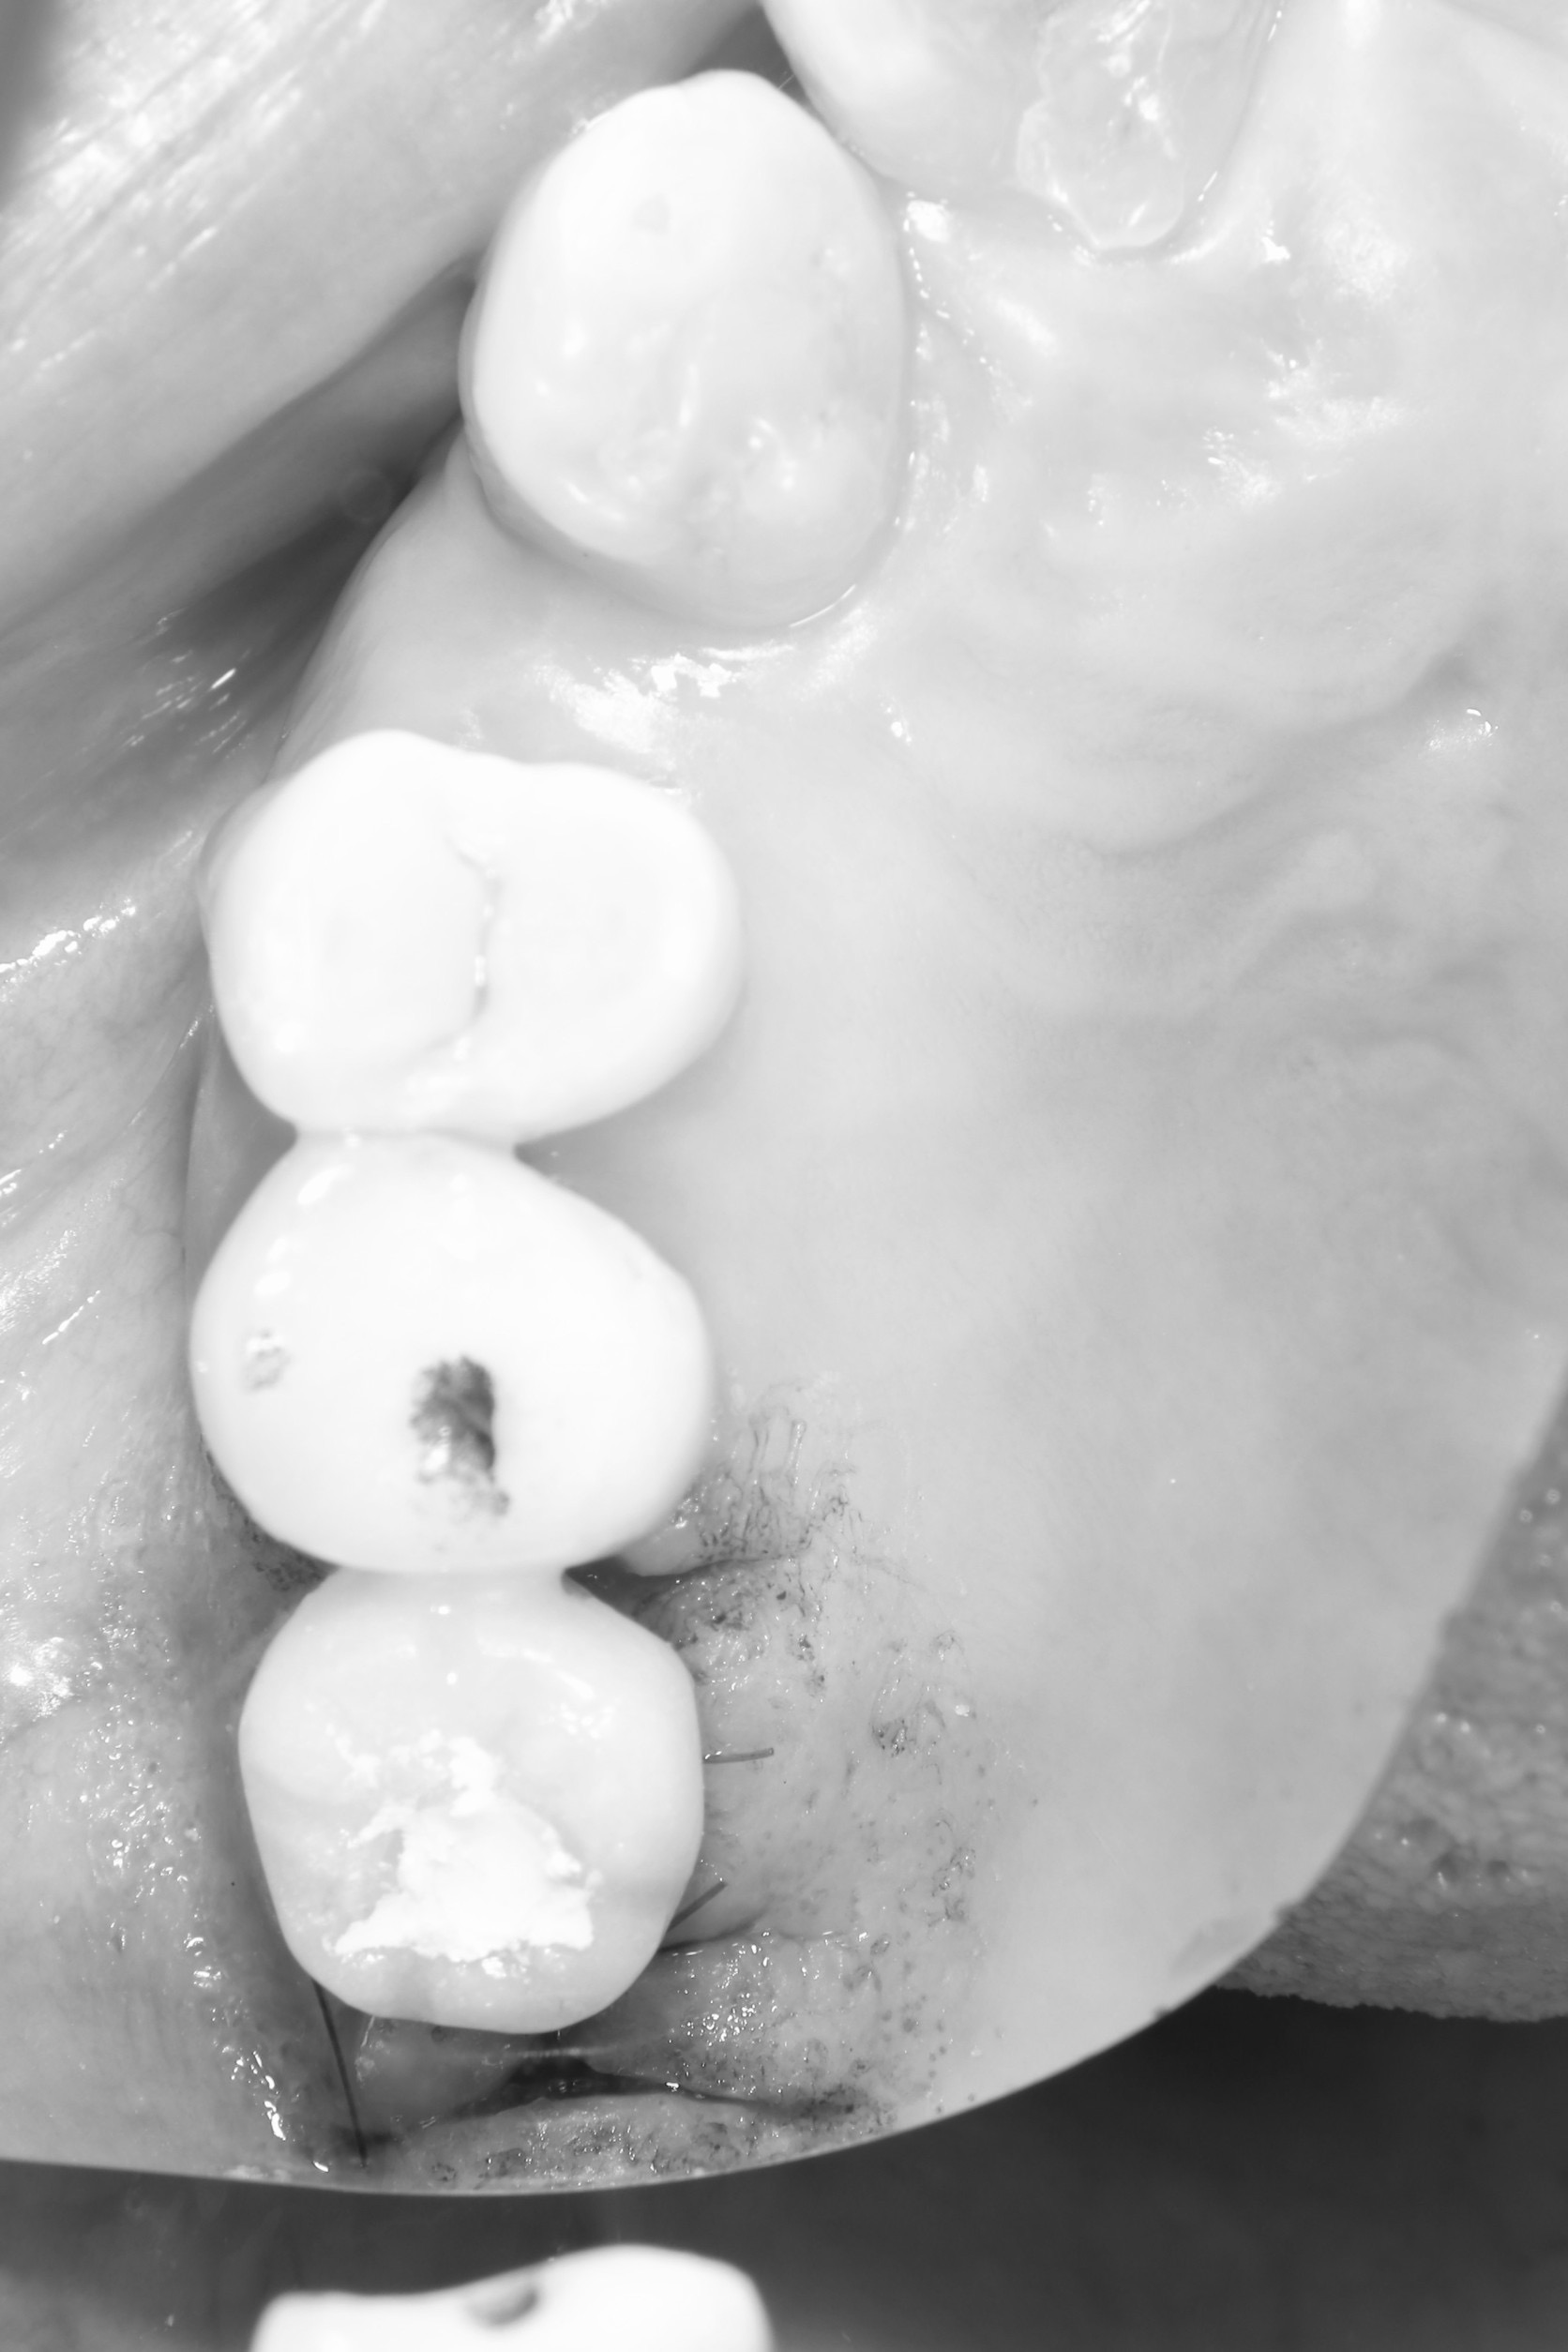

さて、午後からは右上6番のソケットリフトのインプラントオペ

既存骨は4ミリ

最近では、骨高さが3ミリ以下の場合しか人工骨は使いません

この患者さんは、既存骨が4ミリもあるので、デンサーバーだけでの挙上

基準となる、埋入トルク値とISQ値も大変良く

即時に仮歯まで!